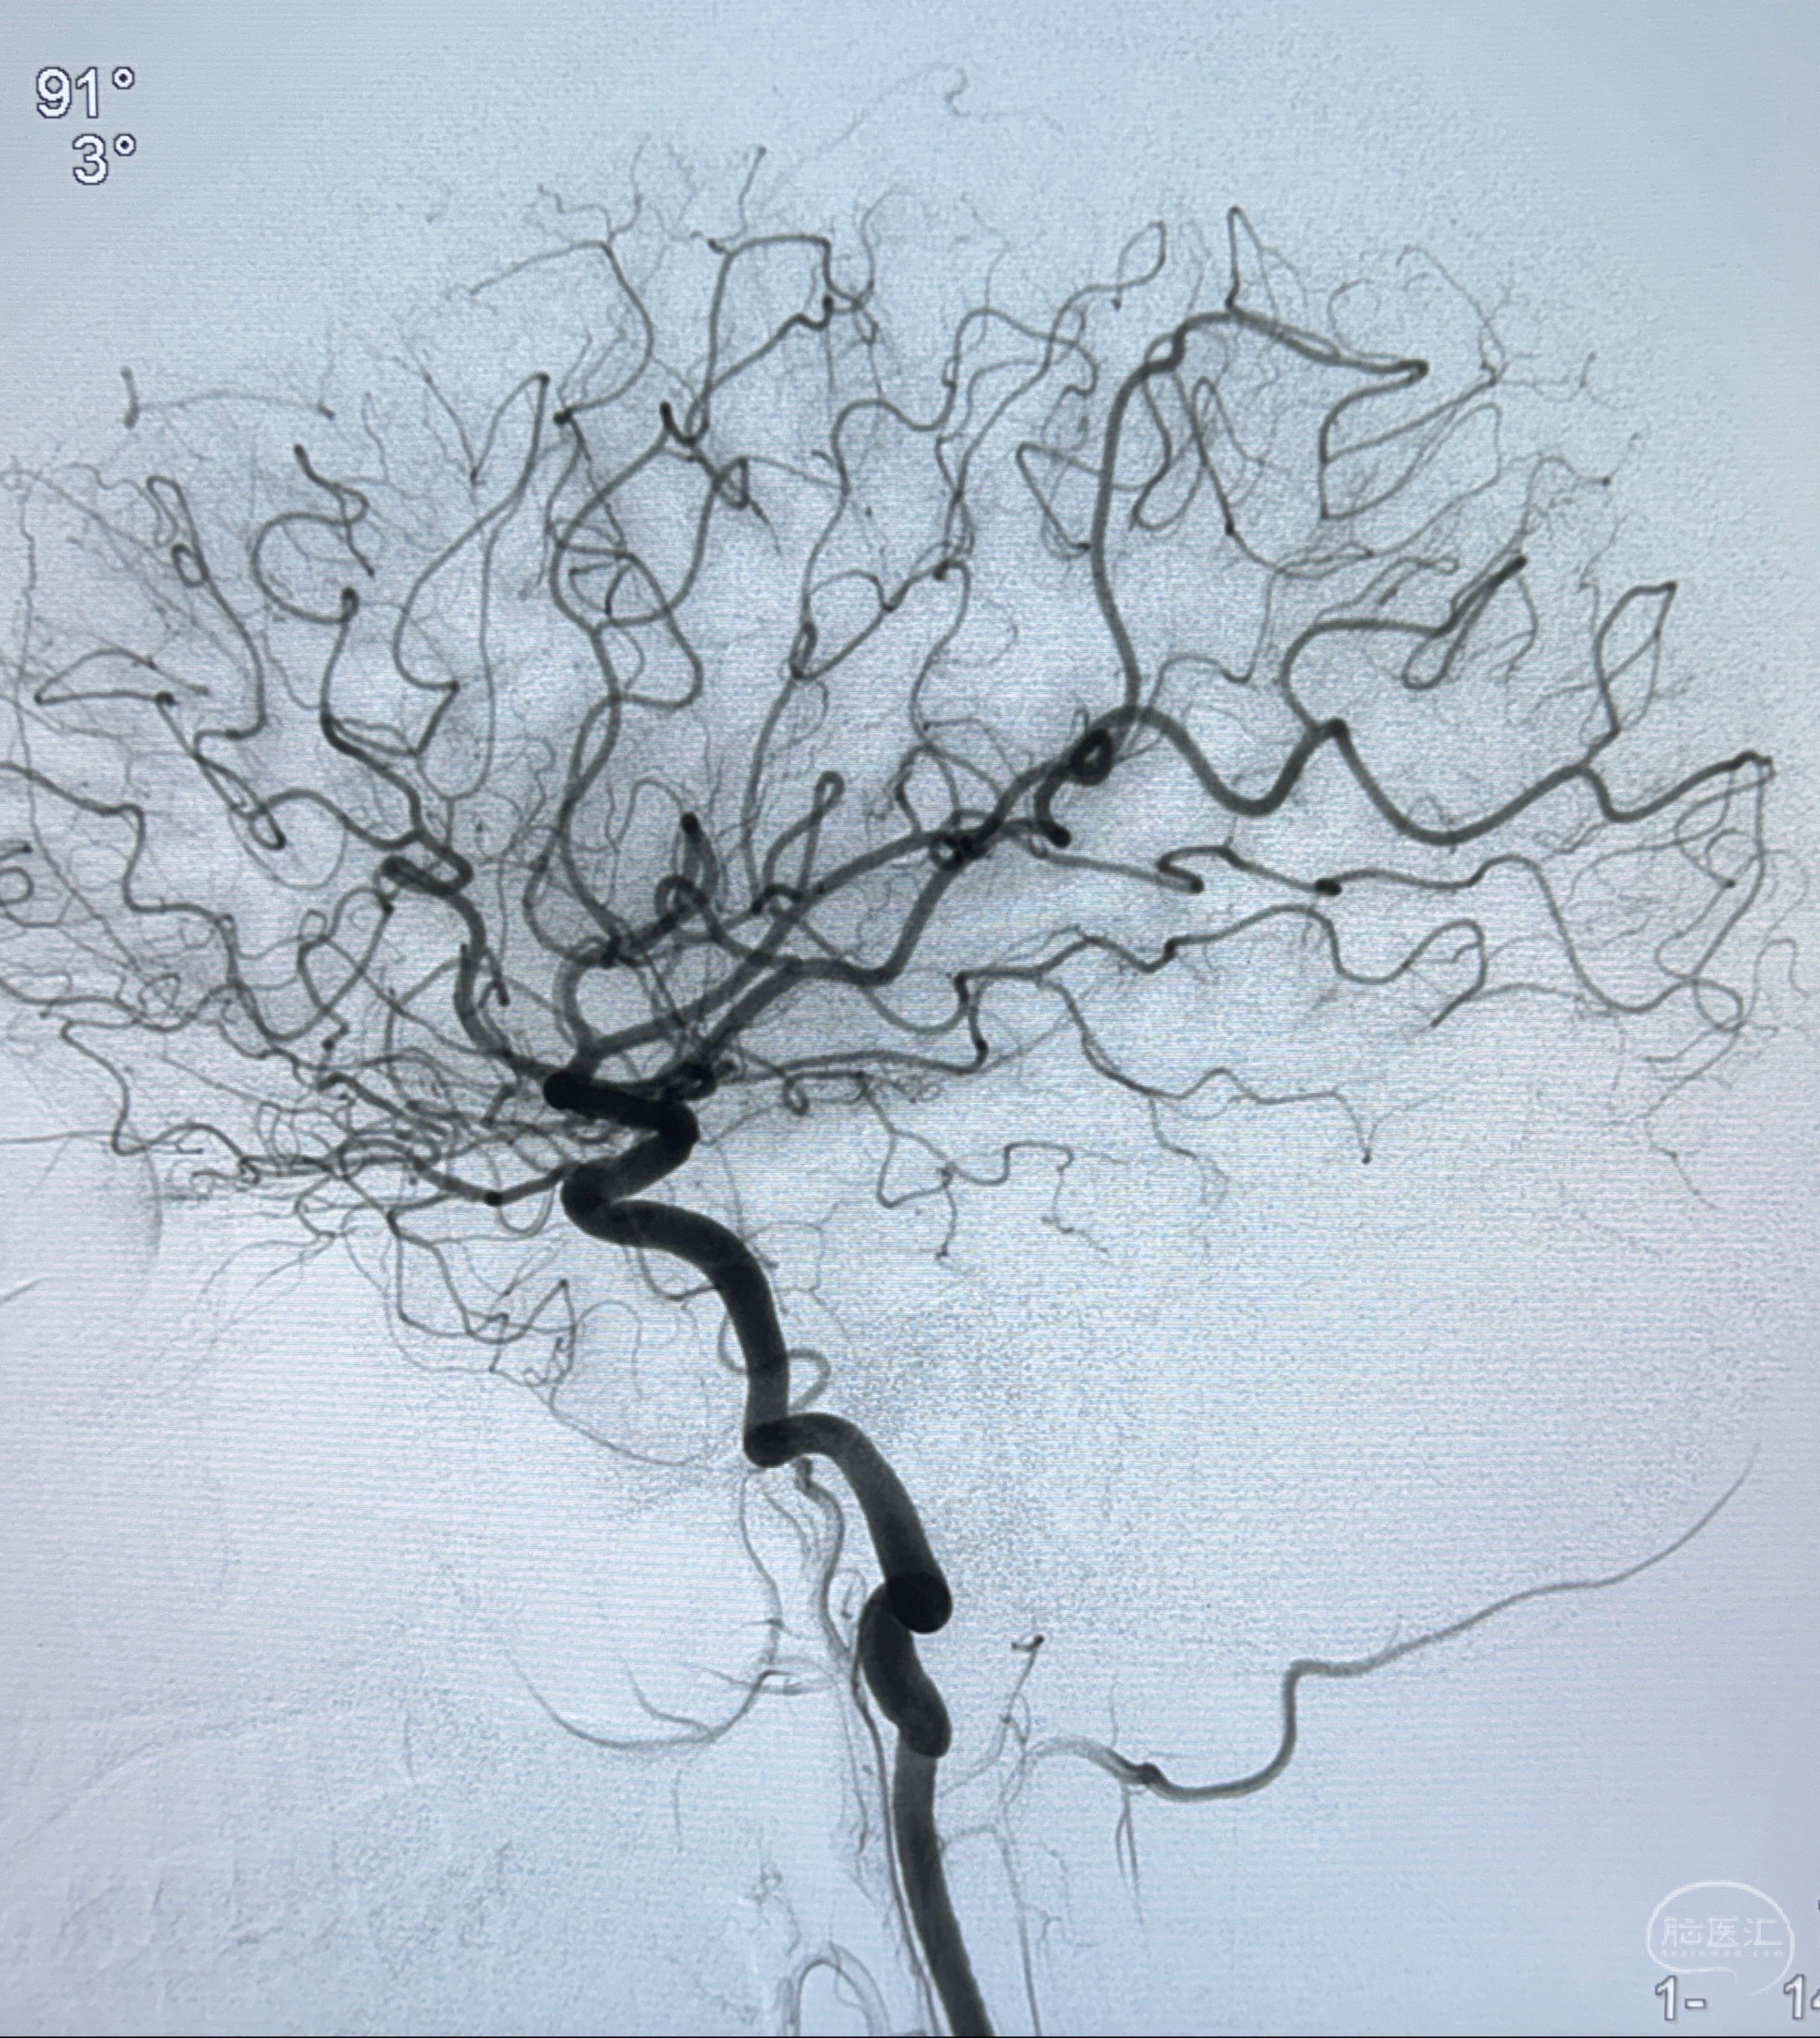

2023-11-13DSA:左侧颈内动脉眼动脉后壁动脉瘤

2023-11-29全麻下行NeuroformEZ4.5-20mm支架辅助栓塞